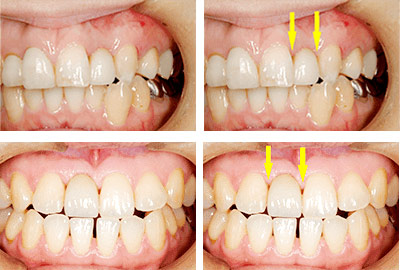

非常に高いレベルの審美性(見た目の美しさ)は目指しません。見た目の美しさについても、可能な限り配慮しますが、患者様の要求されるものと差が生じることがあり、患者様の100%の満足が得られない場合もあるために、超審美的と言われるような美しさはお約束できないと、説明させていただいています。それでも、患者様にご納得いただける程度のレベルの審美性は、達成できていると考えています。

例えば、-

上顎前歯2本のうち向かって右の歯がインプラントなのですが、歯肉がわずかに上にあがってしまい、全くの左右対称にはできずに、右の歯の方が少し長くなってしまっています。

-

もう少し長くなっていますが、口唇を上に引っ張らない限りはそれが見えません。

一見それほど問題にならない程度には仕上がっていますが、隣の歯との間、歯肉の間に空間が残っており、中にはご満足いただけないこともあります。幸いにして、この患者様方には、あらかじめ、見た目についてのご説明をさせていただいた上で、治療を始めていますので、ご納得いただいております。

審美性をさらに高め、天然歯とまったく区別ができない様にしようと思えば、追加の費用をいただいて、歯肉の移植術を行なうなど、方法はありますが、その患者様のお考えになるレベルが様々で、ご満足いただけない場合もあり、当院では、非常に高度な審美性はお約束できないと、ご説明させていただいています。

上記の4例とも、手術費用インプラント1本分15万円(税込16万5000円)、上部構造1歯分20万円(税込22万円)、合計35万円(税込38万5000円)でした。初診から上部構造完成まで治療期間4~5か月かかっています。リスクと副作用